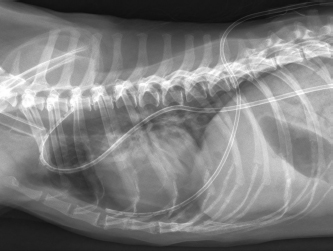

CT imaging revealed a mild bilateral pneumothorax and a roundish radiolucent, bullous, subpleural air-filled structure at the caudo-ventral aspect of the right middle lung lobe at the level of the 6th to 7th intercostal space with a size of 1.8 × 1.8 × 1.4 cm (Fig. 3).

Additionally, a mild to moderate bilateral subcutaneous emphysema and pneumomediastinum were detected bilaterally at that level (Fig. 4). Mild to moderate atelectasis of the right middle, right caudal, and accessory lung lobe was evident in the ventral aspect of the respective lung lobes.

Fig. 4. Transverse CT-image of the thorax at the level of the 5th rip (lung window). A 1.8 × 1.8 × 1.4 cm radiolucent, bullous, air-filled structure within the caudo-ventral aspect of the right medial lung lobe is visible; the air-filled cavity is located at the periphery of the respective lung lobe and seems surrounded by a thin soft tissue dense margin. Additionally, mild bilateral pneumothorax, as well as mild to moderate pneumomediastinum and bilateral subcutaneous emphysema are visible.